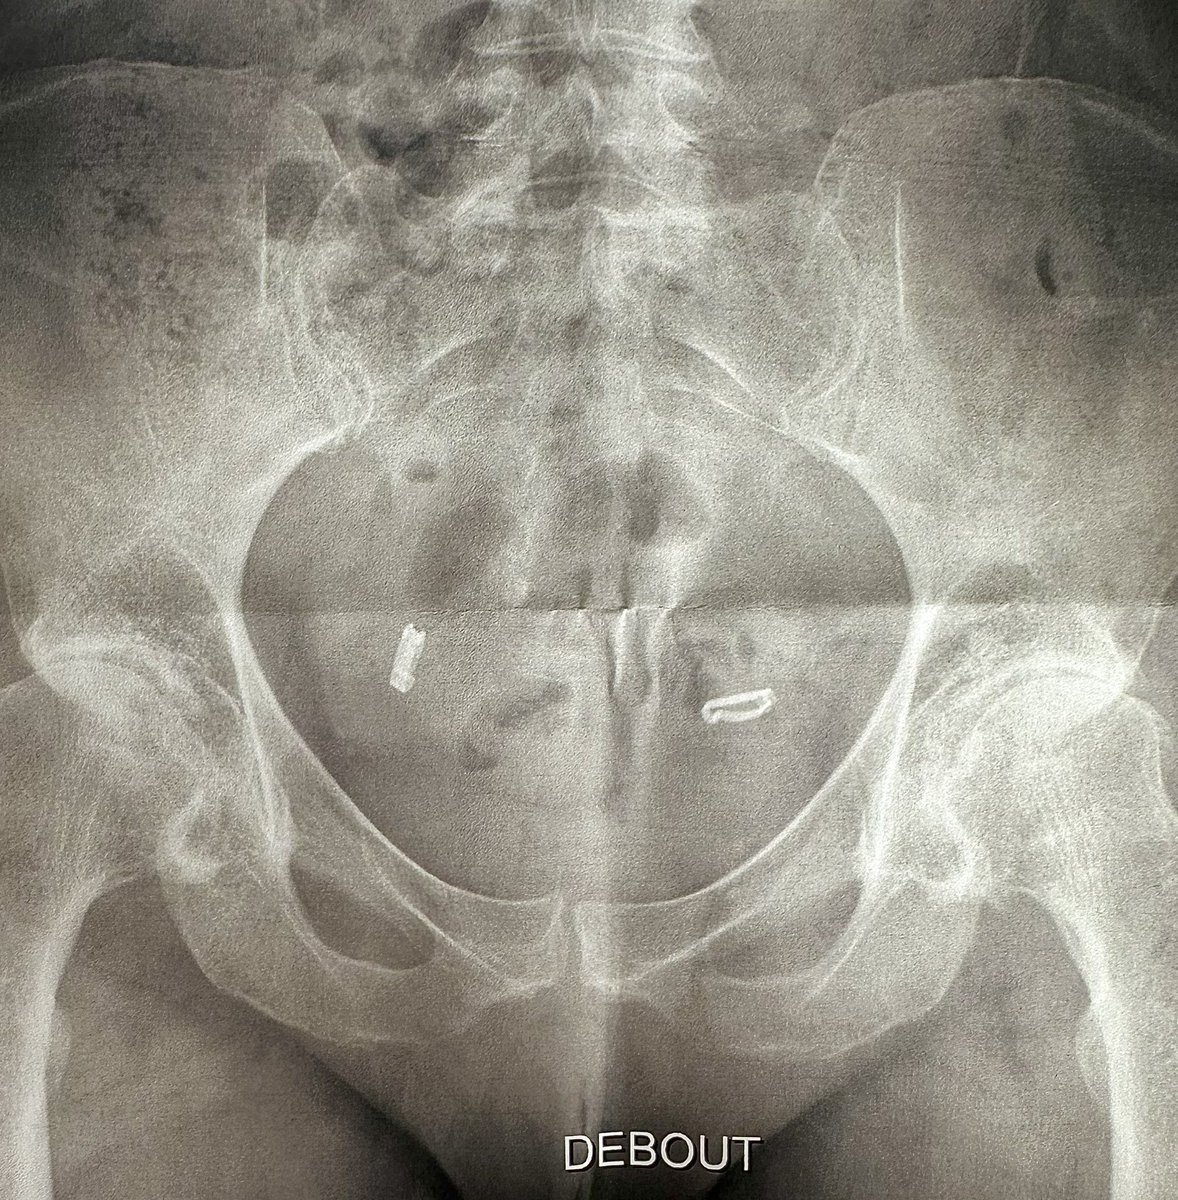

Vid 2. So the july 11th was surgery. This july 13 postop. Swelling was starting. Got tad uncomfortable. Elevate and ice. Hydrate best you can. My appetite was gone! #hipreplacements #postoperation #recovery #surgery #Healing #myjourney #sheilableck #athletes